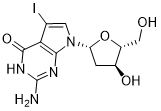

馬鞍山致研生物醫(yī)藥科技有限公司成立于馬鞍山市鄭浦港新區(qū)現(xiàn)代產(chǎn)業(yè)園。公司專(zhuān)注于生物小分子、醫(yī)藥中間體相關(guān)產(chǎn)品的研發(fā)和生產(chǎn),產(chǎn)品主要包括DNA亞磷酰胺單體、RNA亞磷酰胺單體、特殊單體以及按照客戶(hù)要求定制的RNA和DNA,并且公司提供定制合成等方面的研究服...

馬鞍山致研生物醫(yī)藥科技有限公司成立于馬鞍山市鄭浦港新區(qū)現(xiàn)代產(chǎn)業(yè)園。公司專(zhuān)注于生物小分子、醫(yī)藥中間體相關(guān)產(chǎn)品的研發(fā)和生產(chǎn),產(chǎn)品主要包括DNA亞磷酰胺單體、RNA亞磷酰胺單體、特殊單體以及按照客戶(hù)要求定制的RNA和DNA,并且公司提供定制合成等方面的研究服...